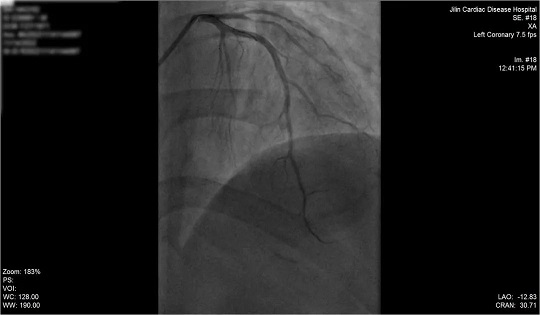

术前冠脉造影

入院后,我院心内科团队争分夺秒进行救治,第一时间为患者行冠状动脉造影检查,锁定冠状动脉左前降支为罪犯血管,心内科Sirbu医生当机立断,为患者先进行冠状动脉血栓抽吸术,将血管中血栓吸出,随后成功于病变处植入1枚支架。从入院到抢救成功,仅用时50分钟。